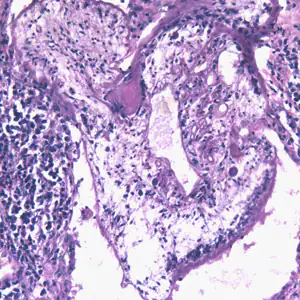

Migrating spargana cause various symptoms depending on the final location in the host. Spargana may locate anywhere, including subcutaneous tissue, breast, orbit, urinary tract, pleural cavity, lungs, abdominal viscera and the central nervous system. The migration in subcutaneous tissues is usually painless, but when spargana settle in the brain or spine a variety of neurological symptoms may occur, including weakness, headache, seizure, and abnormal skin sensations, such as numbness or tingling. If the inner ear is involved, the patient may experience vertigo or deafness. Occasionally, Sparganum proliferum can cause proliferative lesions in the infected tissue, with multiple plerocercoids present in a single site.

Proliferating spargana in lung tissue.